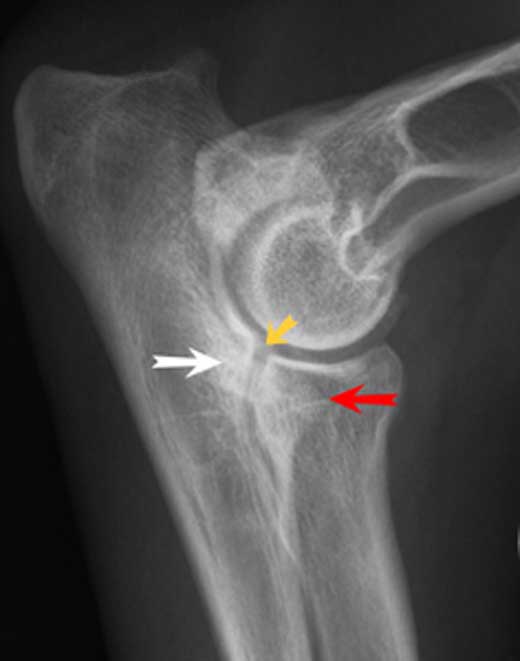

Eine Ellenbogendysplasie entsteht, wenn die gelenkbildenden Knochenteile Oberarmknochen, Elle und Speiche nicht exakt genug zueinander passen. Die ungenaue Passform oder Inkongruenz führt zu chronischen Umbauvorgängen am Ellenbogengelenk und den gelenkbildenden Knochenteilen, die zu einer Sklerosierung der Knochen und zur Ausbildung von Knochenauswüchsen führen. Bei geringer Inkongruenz der Gelenkflächen ist die Osteoarthrose das einzige Anzeichen einer Ellbogendysplasie, darüber hinaus können weitere Veränderungen auftreten:

Fragmentierung des Processus coronoideus medialis (FCP, Ablösung des innen liegenden Kronfortsatzes der Elle) Osteochondrosis dissecans am Condylus medialis humeri (OCD, Knorpelablösung am innen liegenden Rollhöcker des Oberarmknochens) Isolierung des Processus anconaeus (IPA, Ablösung des Ellenbogenfortsatzes der Elle)

Ellenbogendysplasie HundEin gleichzeitiges Auftreten mehrerer dieser Komplikationen ist häufig.